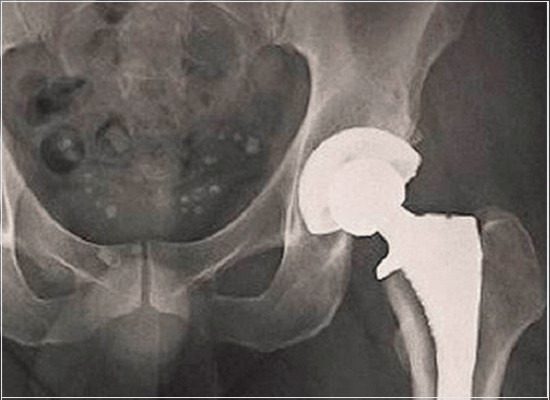

A inspeção radiográfica de componentes metálicos dos implantes para cirurgia